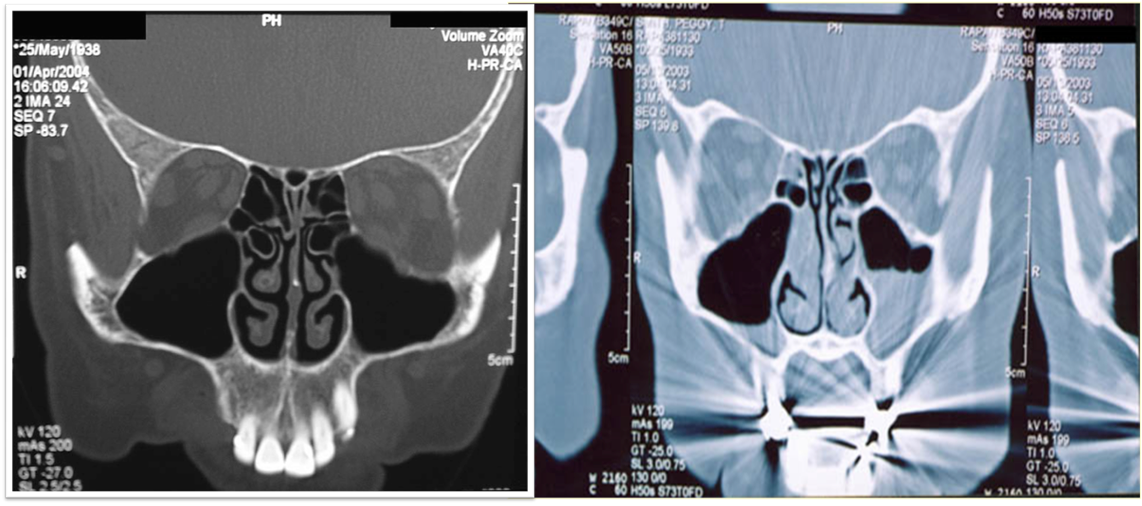

Imaging Study

- Structural abnormality.

- Suppurative complications.

Clinicians should obtain a contrast-enhanced CT scan

of the paranasal sinuses and/or an MRI with contrast whenever a child is suspected of having orbital or CNS complications of ABS